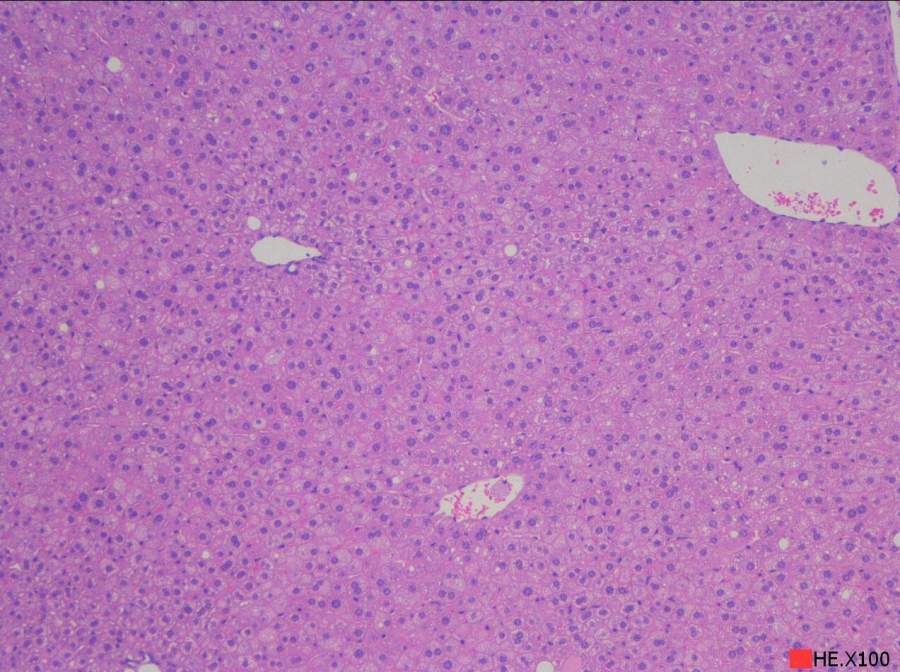

求助读片:小鼠肝脏HE切片(脂肪变性、炎症等)10周龄左右

由于肝脏病变相关知识储备不够,特请教各位虫友帮着读下片,主要想了解肝脏脂肪沉积、变性,是否有炎症等,如果有其它病变也请指点一下。在此不盛感激 !!!下面附图。 2.100.jpg 3.100.jpg 3.200.jpg 4.100.jpg 4.200.jpg 5.200.jpg@starseacow |